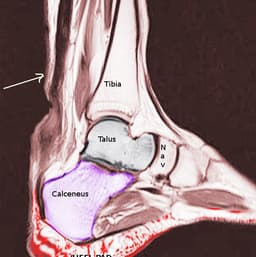

- Achilles tendon rupture usually presents in younger, healthy patients after a sports injury

- Patients typically present complaining of an abrupt onset ankle pain after feeling a "pop"

- Pain can be localized to posterior ankle and patient's lack the ability to plantarflex

- Achilles rupture is a clinical diagnosis and does not usually require imaging in the ED

- Thompson test

- Having patient lay on their stomach and squeezing the calf on the injured side should result in plantarflexion

- If the Achilles is ruptured, no plantarflexion will occur